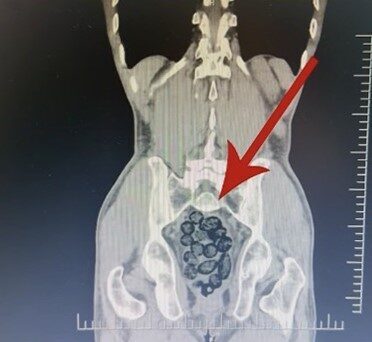

Şüphe üzerine, yabancı uyruklu bir yolcu üzerinde arama yapıldı. Yapılan incelemeler sonucunda, yabancı uyruklu şahsın midesinde 64 parça halinde toplam 472 gram uyuşturucu maddesi metamfetamin bulunduğu belirlendi.

Gözaltına alınan şahsın midesindeki uyuşturucu madde çıkarıldı. Emniyetteki işlemlerinin ardından adliyeye sevk edilen şahıs, çıkarıldığı mahkemece tutuklanarak cezaevine gönderildi.